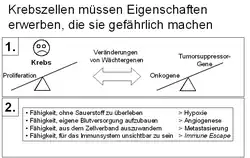

Etwa 5.000 der insgesamt 25.000 Gene des Menschen sind für die sichere Erhaltung der Erbinformation von einer Zellgeneration zur nächsten zuständig. Diese sogenannten Tumorsuppressorgene überwachen die korrekte Abfolge der Basenpaare in der DNA nach jeder Reduplikation, entscheiden über die Notwendigkeit von Reparaturvorgängen, halten den Zellzyklus an, bis die Reparaturen ausgeführt sind, und veranlassen gegebenenfalls einen programmierten Zelltod (Apoptose), falls die Reparatur nicht zum Erfolg führt. Daneben sind die Protoonkogene zuständig für die Einleitung oder den Unterhalt der Proliferation der Zelle und ihrer anschließenden Entwicklung zu einem bestimmten Zelltyp (Differenzierung).

Nach der heute als plausibel geltenden Theorie der Krebsentstehung (Karzinogenese) ist das primäre Krankheitsereignis eine Veränderung in einem dieser Wächtergene – entweder durch einen Kopierfehler oder seltener durch eine angeborene Mutation. Dieses Gen kann dann den von ihm überwachten Teilschritt nicht mehr korrekt begleiten, sodass es in der nächsten Zellgeneration zu weiteren Defekten kommen kann. Ist ein zweites Wächtergen betroffen, so potenziert sich der Effekt fortlaufend. Wenn auch Apoptose-Gene (z. B. p53) betroffen sind, die in einer solchen Situation den programmierten Zelltod auslösen müssten, werden diese Zellen potentiell unsterblich. Durch die Aktivierung der Protoonkogene wird ein Krebs zum Wachstum angeregt, was in einer Raumforderung und in Folge zu auftretenden Schmerzen führen kann. Zur Krebsentstehung sind mehrere solcher Mutationen notwendig (englisch multiple hit model).[20] Hierbei hat sich die Annahme von Peter Nowell bestätigt, dass zur Entstehung eines malignen Tumors mindestens sechs bis sieben Mutationen nötig sind.[21]

Die Proliferation einer in den relevanten Genen veränderten Zelle zu einem Zellhaufen vergrößert dabei entscheidend die Wahrscheinlichkeit für eine weitere relevante genetische Veränderung im Rahmen des Mehrschrittprozesses, da bei jedem Kopiervorgang der DNA Fehler entstehen können. Solche Veränderungen können auch durch äußere Einflüsse (z. B. krebserregende Stoffe, ionisierende Strahlung, Onkoviren) induziert werden, oder durch eine genetische Instabilität der veränderten Zellpopulation zustande kommen. Irritierende Reize können durch Erhöhung der Proliferation diesen Prozess beschleunigen. Während bei einigen Tumoren eine oder zwei Mutationen ausreichen können,[22] gibt es auch Tumoren, bei welchen bis zu zehn verschiedene Mutationen erfolgt sein müssen. Einige dieser notwendigen Mutationen können vererbt werden, was erklärt, dass auch sehr kleine Kinder an Krebs erkranken können und dass Krebs in sogenannten „Krebsfamilien“ gehäuft auftreten kann. Ein typisches Beispiel dafür ist das vererbbare Xeroderma pigmentosum. Bei nahen Verwandten von Patientinnen mit Brustkrebs ist die Wahrscheinlichkeit, Brustkrebs zu bekommen, doppelt so hoch wie in der übrigen Bevölkerung. In den dazwischenliegenden Schritten der Tumorentstehung (Promotion und Progression) spielen nicht genotoxische Prozesse eine große Rolle, was Beobachter dazu verleiten könnte, diese Einflüsse als eigentliche „Krebserreger“ einzustufen.

Durch weitere Veränderungen der DNA kann die Zelle zusätzliche Eigenschaften ausbilden, die eine Behandlung der Krebserkrankung erschweren, darunter die Fähigkeit, unter Sauerstoffmangel zu überleben, eine eigene Blutversorgung aufzubauen (Angiogenese) oder aus dem Verband auszuwandern und sich in fremden Geweben wie Knochen (Knochenmetastase), Lunge (Lungenmetastase), Leber (Lebermetastase) oder Gehirn (Hirnmetastase) anzusiedeln (Metastasierung). Erst durch diese Fähigkeit gewinnt der Krebs seine tödliche Potenz: 90 % aller Krebspatienten, bei denen die Krankheit tödlich ausgeht, sterben nicht am Primärtumor, sondern an den Folgekrankheiten der Metastasierung.

Mehrschrittmodell bzw. Dreistufenmodell

Die meisten Krebsforscher gehen vom sogenannten ‚Mehrschrittmodell‘ der Krebsentstehung aus. Das Mehrschrittmodell versucht die Krebsentwicklung ursächlich zu verstehen. Hierbei entspricht jeder einzelne Schritt einer bestimmten genetischen Veränderung. Jede dieser Mutationen wiederum treibt die stufenweise fortschreitende Verwandlung einer einzelnen normalen Zelle in hochmaligne Abkömmlinge voran (Maligne Transformation).[27] Die eigentliche Malignität (Bösartigkeit) der entarteten Zelle wird in der Phase der Progression erreicht. Die Begriffe Promotion und Progression werden zunehmend vom Begriff der Co-Karzinogenese ersetzt.